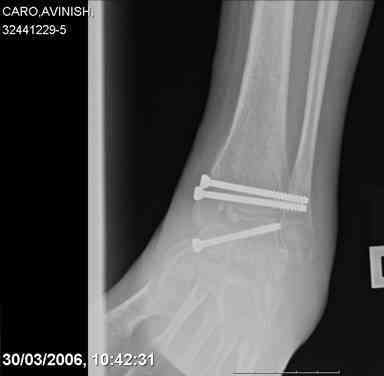

ya by popytalsya sobrat talus anatomichno,seichas pozdno operirovat iz za oteka,po etomy distrakziya apparatom budet optmalna.Posyalu vam podobyai moi sluchai.

14 years old girl

Fall from height ( 3rd floor)

Compressed fractures of L1-L2

Fx of orbital bone

Mark, судя по снимкам в день поступления произведен А.В.Ф., а остеосинтез ч-з какое время произведен?, остеосинтез произвели открытым способом?( на снимке п/о рубцы).

aparat postavlen v den postupleniya,rastaynuli, vpravili zakryto naskolko vozmoghno, a kogda otek spal sdelali otkrytoe vpravlenie.Teryat tut nechego, moghno tolko uluchshit.